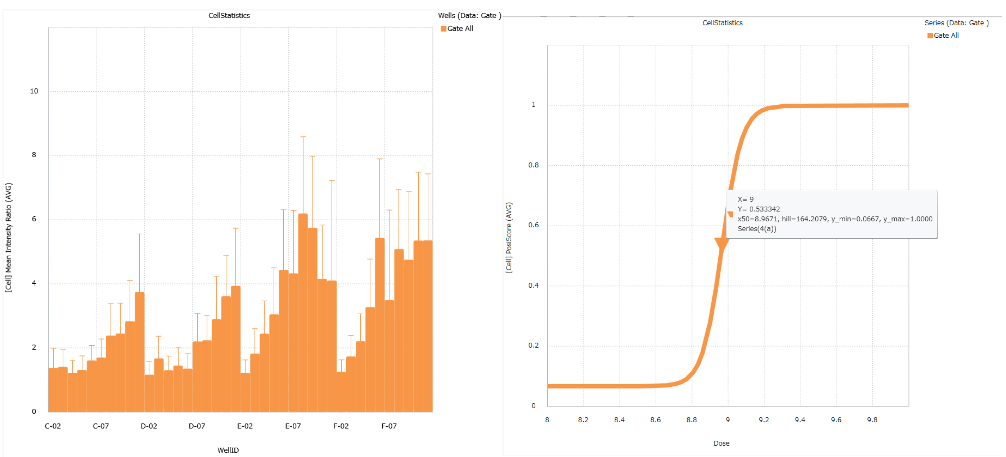

Convenient graphing tools

Image Credit: Yokogawa Life Science

The analysis findings can be shown as a bar chart, line chart, pie chart, scatter plot, heatmap, or histogram. The results can also be estimated using the EC50, IC50, and Z'-factor.

Convenient graphing tools

Image Credit: Yokogawa Life Science

An analysis's findings can be shown using a histogram, bar chart, scatter plot, pie chart, heatmap, and bar chart. The results can also be estimated using the EC50, IC50, and Z'-Factor.